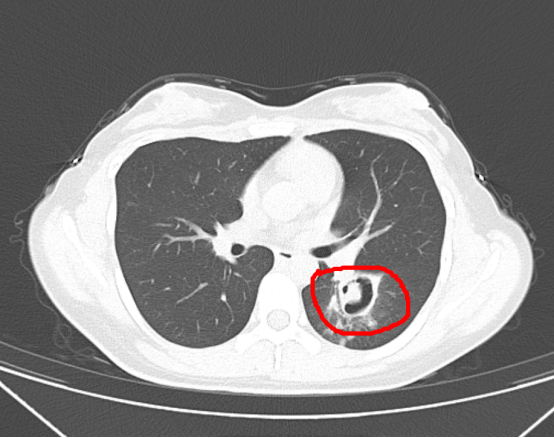

到医院检查后

被诊断为霉菌性肺炎

为了进一步确诊病情

医生为她做了纤维支气管镜检查

发现气道壁上缀着大量白色菌斑

化验后确认是曲霉菌